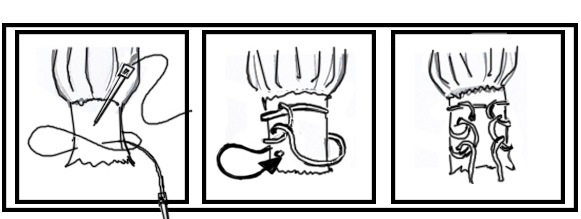

Open tendoachilles repair

Technique

- Bunnell Suture / Krackow suture x 2 with high strength suture / fibre wire

- one in proximal and one in distal tendon ends

- tie via two knots with foot fully plantar flexed

- +/- augment with circumferential 4.0 suture to minimize bunching

- careful closure of paratenon to prevent skin adhesions

Anterior release of paratenon to allow posterior closure over achilles repair

Repair with proximal and distal Krackow high strength sutures